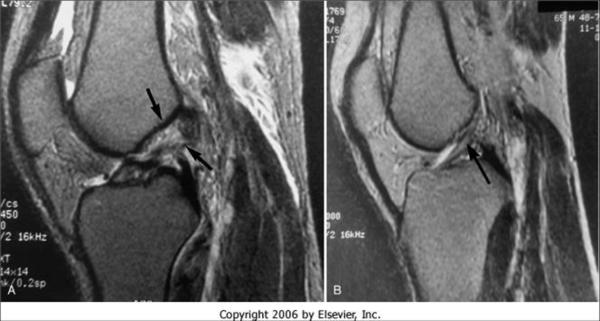

核磁表現(xiàn)

全斷裂

直接征象

1、連續(xù)性中斷(所有層面找不到一個(gè)完整的ACL)

2、韌帶增粗呈團(tuán)塊狀、 ACL內(nèi)形成假瘤,T1WI低信號(hào)、T2WI 高低混雜 見(jiàn)不到完整的纖維束。

3、邊緣不規(guī)則、成角扭曲呈波浪狀(MRI連續(xù)性未見(jiàn)中斷、鏡下用探子探察全斷)

4、T2WI彌漫性高信號(hào)